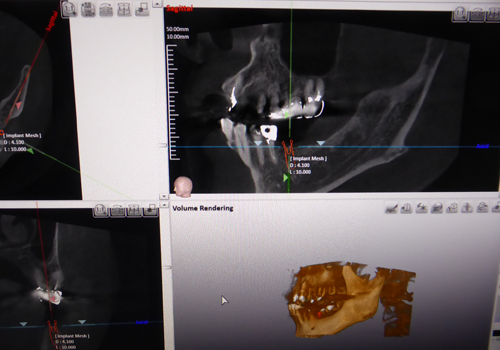

インプラント治療

しかし歯周病などの原因で骨が少ないケースがあります。骨の量を確認するためにCTは必要となります。

下の奥歯にインプラント処置をする場合、下歯槽神経などの重要な神経を傷つけないために下歯槽管の位置を確認するために使用します。